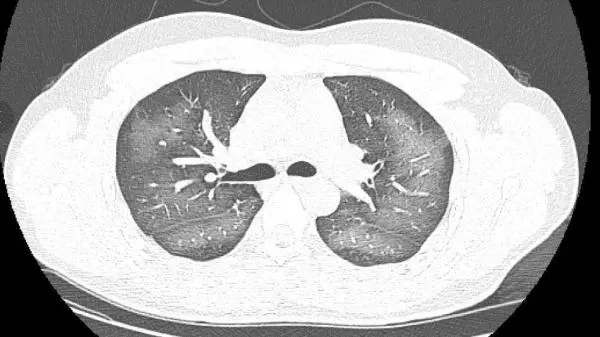

光明網發表於2023年8月4日的一篇報道,記錄了湖南一位患者使用防曬噴霧導致“白肺”。所謂“白肺”,即重症肺炎在X線或者CT檢查中,患者肺部呈現大片白色狀態,一般常見於高齡、免疫力低下等人羣。

而報道中的這名患者是年輕人,導致其“白肺”的罪魁禍首正是使用防曬噴霧。據報道,這名湖南小夥一天外出時對着自己臉使用了防曬噴霧,但是不小心誤吸,之後出現胸悶、咳嗽症狀。並且症狀一直持續到第二天仍未好轉,前往就醫才發現已經“白肺”。

最終在醫生給予吸氧、化痰、抗感染治療等措施後,患者症狀明顯改善。